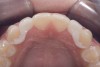

(14.) Occlusal view. Some form of augmentation would be needed if implants were being considered.

Figure 14

Some patients do not want an implant due to the need for surgical intervention, and others may not have enough space for implant placement. A 15-year-old patient presented to the office after completion of orthodontic treatment to idealize the spacing of her teeth and improve her occlusal relationship (Figure 12 through Figure 14). Because both of her maxillary lateral incisors were missing, the patient was wearing a retainer with lateral incisor pontics. She had a busy school schedule, but expressed her desire for a fixed restorative option. All of her options were discussed, and the patient was informed that if she wanted an implant, she would have to wait for at least 3 to 4 years for completion of growth. The patient was not sure if or when she wanted to have an implant placed in the future, especially considering her busy schedule and desire to attend college after high school. Considering her age and the need to be conservative, a single-wing zirconia Maryland Bridge was chosen as the ideal prosthetic replacement option. Because bonding a non-etchable and smooth surface such as zirconia requires chemical adhesion, it was decided to use a modified technique to make the bridge more retentive. One of the ways to improve adhesion of a zirconia bridge is to use an etchable feldspathic ceramic layer on the internal surface of the zirconia retainer.56-58 Unfortunately, it can be difficult to determine the thickness of the ceramic and ensure accurate seating of the restoration.